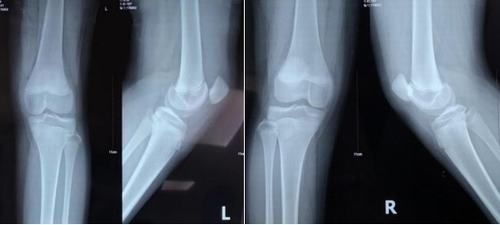

X线片示:髌骨脱位